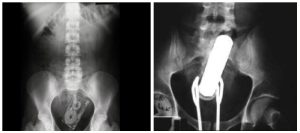

Gioco erotico finito male, operato d’urgenza con flacone di deodorante nel retto

Un gioco erotico finito male, decisamente male. Un uomo è stato operato d'urgenza dopo che un flacone di deodorante è...